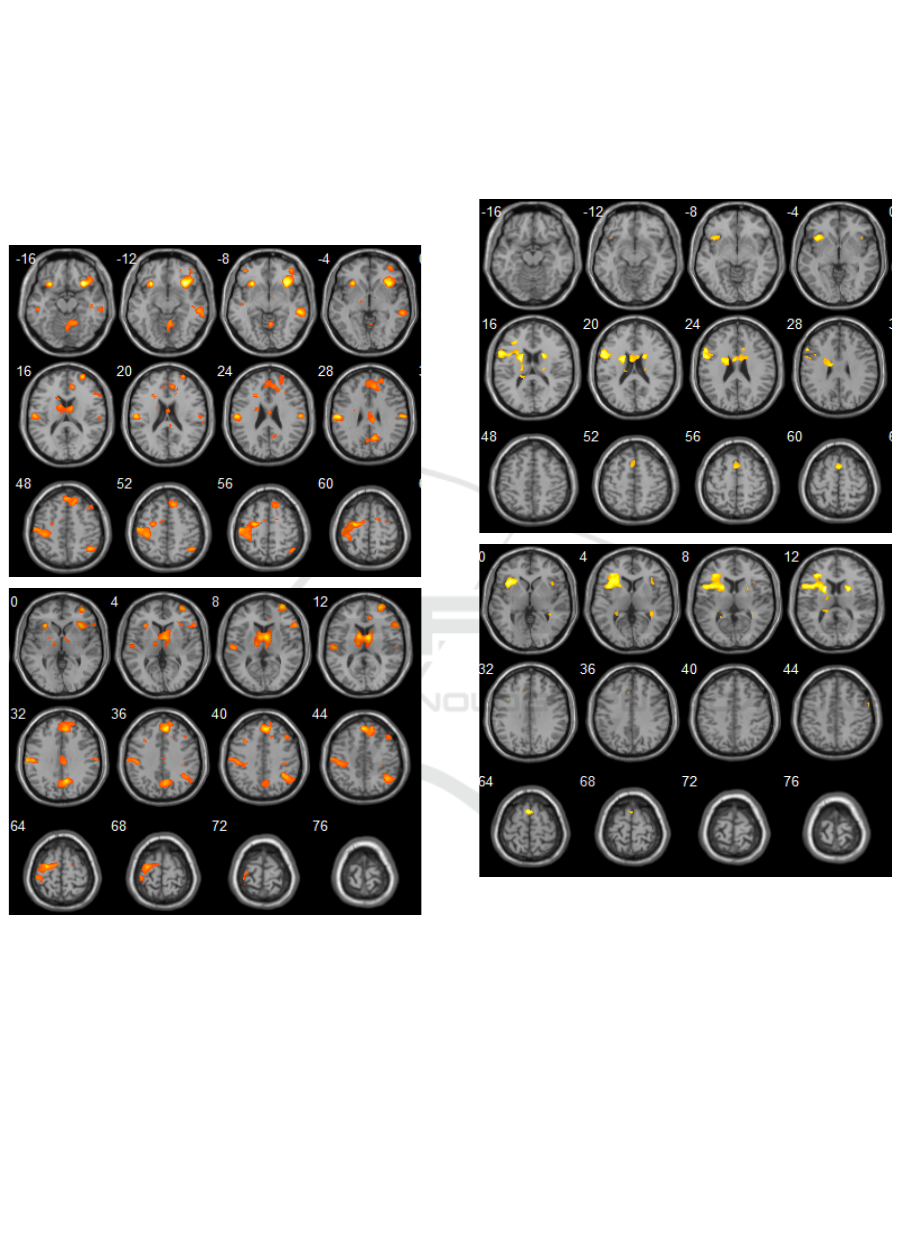

When performing intragroup analysis (healthy

volunteers) at the stages of interaction of neuronal

structures for recognizing the presented images, a

decrease in activation was detected in the prefrontal

cortex, the Broadman area (BA) 10, as well as in the

projection of BA17 and BA18 (MNI coordinates: -36 -

90 14). At the same time, an increase in activation was

observed in the isthmus of the cingulate gyrus - BA31

(MNI coordinates: 6 -62 32), in the insula (MNI

coordinates: 4 40 38) and the parahippocampal gyrus

(MNI coordinates: 32 -36 -12). Local patterns of

processing visual information, recognizing visual

images and transmitting information to other

departments of the visual analyzer that are involved in

providing emotional-volitional decisions, the

formation of motivation, cognitive flexibility, short-

Figure 1: The control group. Activation sites (response to a

visual stimulus) in the projection of brain structures: the

isthmus of the cingulate gyrus, insular cortex,

parahippocampal gyrus, Broca and Wernicke areas

bilaterally.

term memory and neurodynamics, which is the main

function of the thalamo lenticular complex (Figure 1),

As it can be seen in Figure 2, when performing a

speech test, there were activations in the region of the

parahippocampal complex in the projection of the

fusiform gyrus (MNI coordinates: 30 -34 20), upper

and lower temporal gyri on the right (MNI coordinates:

52 64 22; 54 -18 -22), upper frontal gyrus on the right,

caudate nuclei (MNI coordinates: 6 8 -6), insular lobes

(MNI coordinates: 34 -22 10).

Figure 2: The control group. Activation sites (response to a

speech test) in the projection of brain structures: the isthmus

of the cingulate gyrus, insular lobes and parahippocampal

gyri.

Presenting a ”count” stimuli resulted in activation areas

in the projection of the middle frontal gyri bilaterally,

insular cortex on the right (MNI coordinates: 40 - 14

8), the upper frontal gyrus on the left (MNI

coordinates: -14 48 48), precentral gyrus bilaterally

(MNI coordinates: 38 -14 50; -24 -24 62). All these

zones are parts of the working network of the brain

at rest and carry out complex, including logical,

processing of information of various nature, are

responsible for short-term and long-term memory,

fluency of speech, neurodynamics, and error control

Figure 3: The control group. Activation sites (response to a

count test): in the projection of brain structures: medial

prefrontal cortex, BA9, BA46, BA31, BA32.

(Figure 3).

The dynamical intergroup analysis was aimed to

establishing statistically significant differences

between the volume of activations to compare

functional changes in the cerebral cortex in patients

with AVM and healthy volunteers. In patients with

AVM, fewer activation sites were detected in

response to certain cognitive tasks. Recognition of the

presented images, storing and fixing of repeated

images on the images presented on the screen

revealed an increase in the activation of the following

areas of the brain in patients with AVM: on the left is

the region of the central gyrus, subcortical structures

BA6 (MNI coordinates: -2 8 -25), BA10 (MNI

coordinates: 23 55 7); parietal cortex (MNI

coordinates: 23 -38 52), on the right - the lower

parietal cortex (MNI coordinates: -24 -50 -40), the

prefrontal cortex (MNI coordinates: 17 44 2) and the

cingulate cortex (MNI coordinates: 4 23 22), p

<0.001, (Figure 4).

When performing a speech test, in patients,

comparing to the control group, a decrease in

activation was found in the following areas: lower

parietal lobe bilaterally, insular lobules on the left

(BA13, MNI coordinates: -42 4 -1), lower frontal

gyrus on the left (MNI coordinates: -32 47 -1),

caudate nucleus (MNI coordinates: 14 10 11) on the

left, parahippocampal gyrus on the left (MNI

coordinates: 24 -9 -4). There was also a statistically

significant increase in activation in the projection of

the superior frontal gyrus on the left (BA 10, MNI

coordinates: 12 49 4), the medial prefrontal cortex

and the anterior cingulate gyrus, p <0.001, (Figure 5).

When performing count test (repeated count

operations), in patients, comparing to the control

group, a statistically significant increase in

activations was established in the following areas:

inferior parietal lobe, BA32 bilaterally (MNI

coordinates: -10 46 11; 14 40 11) , BA7 (MNI

coordinates: 23-60 60), BA9 on the right (MNI

coordinates: 35 39 31), insula (MNI coordinates: 44 4

10), middle frontal gyrus (MNI coordinates: 30 47

11), waist gyrus on the left (MNI coordinates: -3 36

11), p <0.001, (Figure 6).